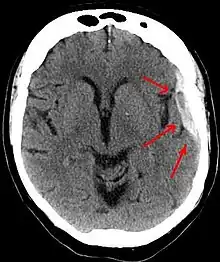

| Subdural hematoma as marked by the arrow with significant midline shift | |

Subdural hematomas occur most often around the tops and sides of the frontal and parietal lobes.[3][2] They also occur in the posterior cranial fossa, and near the falx cerebri and tentorium cerebelli.[3] Unlike epidural hematomas, which cannot expand past the sutures of the skull, subdural hematomas can expand along the inside of the skull, creating a concave shape that follows the curve of the brain, stopping only at dural reflections like the tentorium cerebelli and falx cerebri.

On a CT scan, subdural hematomas are classically crescent-shaped, with a concave surface away from the skull. However, they can have a convex appearance, especially in the early stages of bleeding. This may cause difficulty in distinguishing between subdural and epidural hemorrhages. A more reliable indicator of subdural hemorrhage is its involvement of a larger portion of the cerebral hemisphere. Subdural blood can also be seen as a layering density along the tentorium cerebelli. This can be a chronic, stable process, since the feeding system is low-pressure. In such cases, subtle signs of bleeding—such as effacement of sulci or medial displacement of the junction between gray matter and white matter—may be apparent.

Fresh subdural bleeding is hyperdense, but becomes more hypodense over time due to dissolution of cellular elements. After 3–14 days, the bleeding becomes isodense with brain tissue and may therefore be missed.[20] Subsequently, it will become more hypodense than brain tissue.[21]